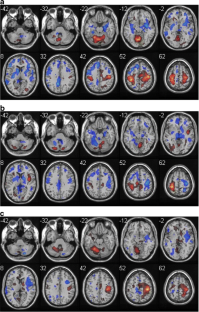

Restoration of motor function following stroke involves reorganization of motor output through intact pathways, with compensatory brain activity likely variable by task. One class of motor tasks, those involved in self-care, is particularly important in stroke rehabilitation. Identifying the brain areas that are engaged in self-care and how they reorganize after stroke may enable development of more effective rehabilitation strategies. We piloted a paradigm for functional MRI assessment of self-care activity. In two groups, young adults and older adults, two self-care tasks (buttoning and zipping) produce activation similar to a bimanual tapping task, with bilateral activation of primary and secondary motor cortices, primary sensory cortex, and cerebellum. Quantitative differences include more activation of sensorimotor cortex and cerebellum in buttoning than bimanual tapping. Pilot subjects with stroke showed greater superior parietal activity across tasks than controls, potentially representing an increased need for sensorimotor integration to perform motor tasks.

Fig. 3